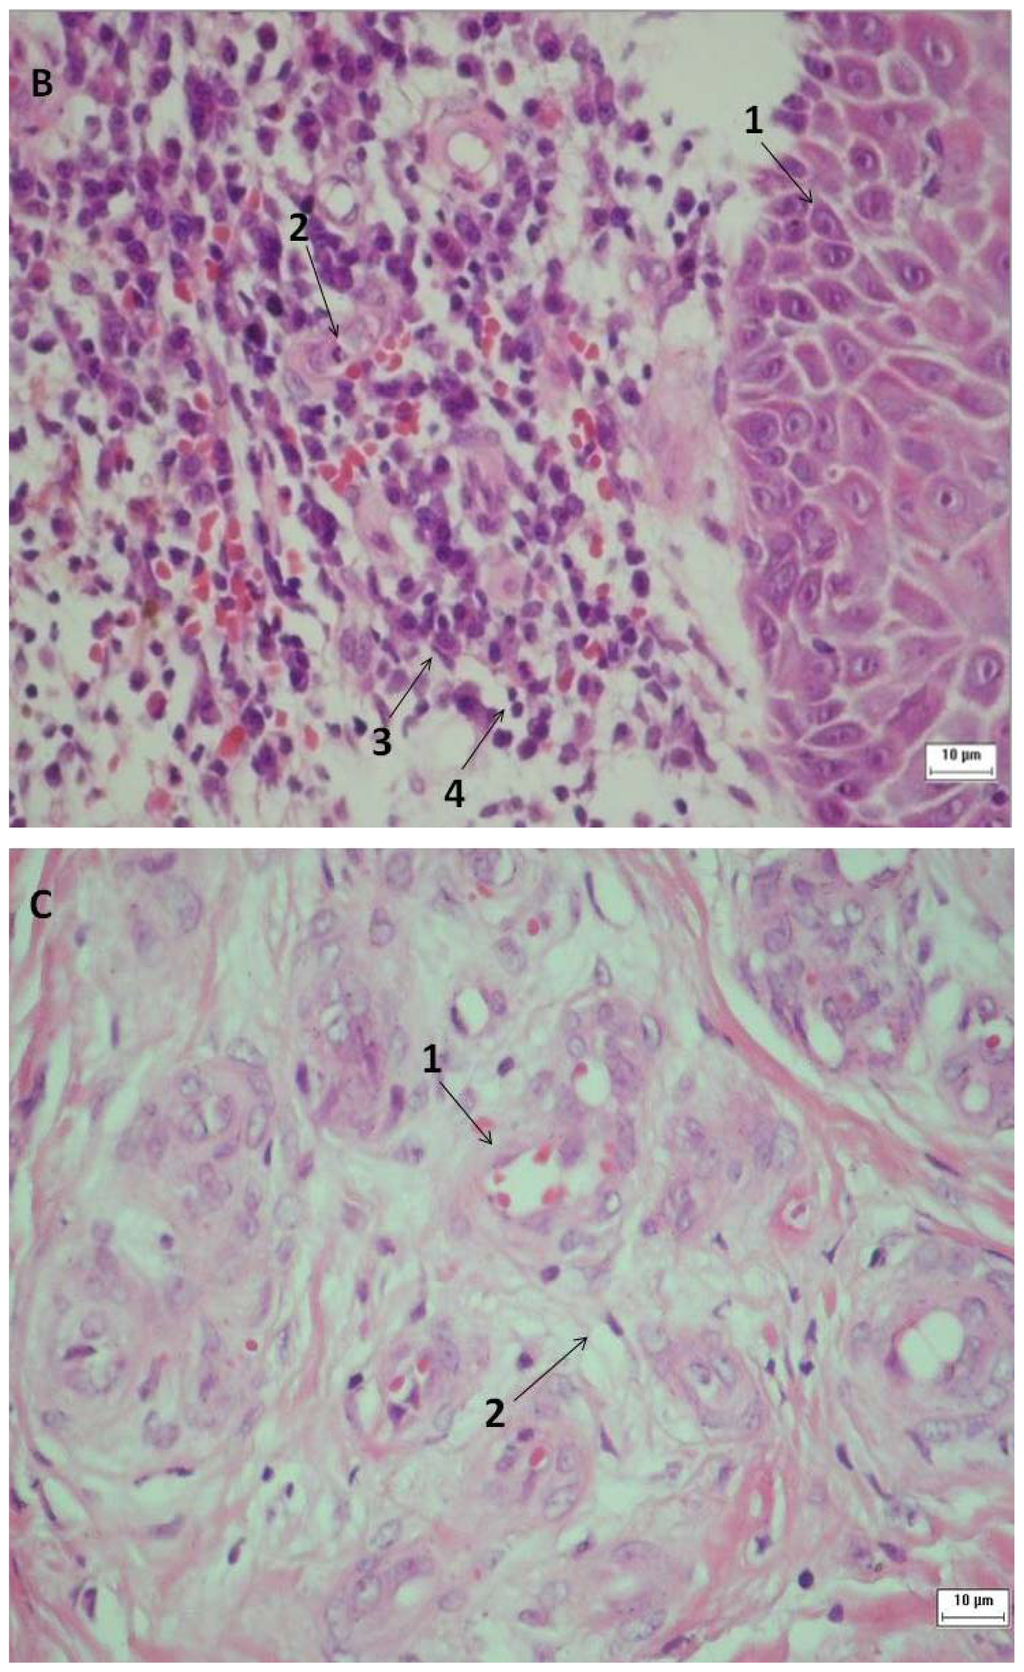

Figure 3.

Histology of the venous ulcers. The tissue was stained with hematoxylin and eosin (H & E) to visualize the cellular morphology. Samples A, B and C were collected prior to (1→3)-β-glucan treatment. The following magnifications are shown: 100 × H & E stain for A; 400 × H & E stain for B and C. (A) The arrow indicates epithelial hyperplasia at the edge of the ulcer. (B) Arrow No. 1 shows reactive and reparative epithelial changes in the stratified squamous epithelium and the other arrows show inflammatory cell infiltration, including neutrophil (arrow No. 2), plasmocyte (arrow No. 3) and lymphocyte (arrow No. 4). (C) Arrow No. 1 indicates angiogenesis associated with edema and arrow No. 2 indicates fibroblast.